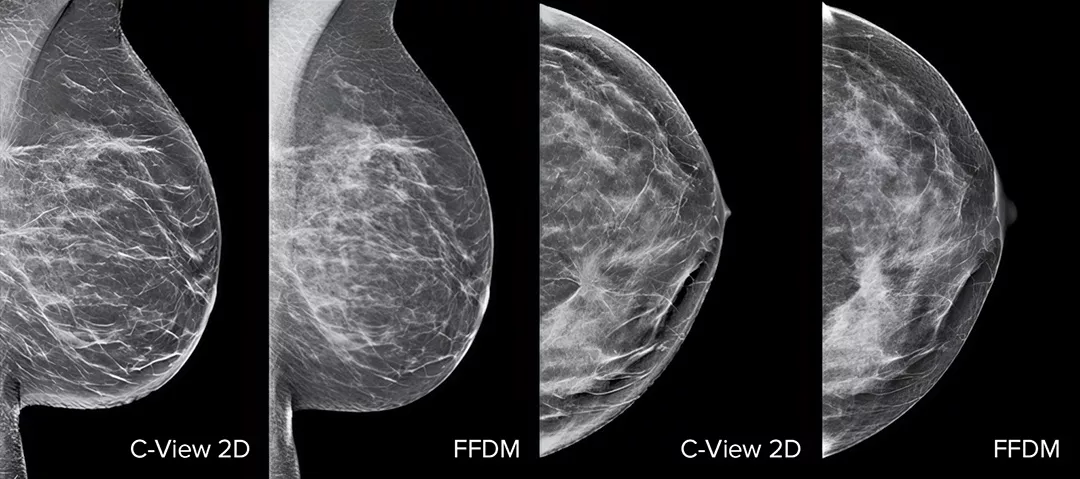

Raise your breast cancer screening performance1-4 with C-View software and instantly generated synthesised 2D images. It not only enhances details and speeds up the analysis, but also reduces radiation dose levels for your patients. C-View 2D images are clinically proven3,5 and FDA approved to diagnostically replace the FFDM images within a tomosynthesis screening exam.

Architectural distortions, mass lesions, and bright spots commonly found in microcalcifications are more visible in the C-View 2D image than on the traditional FFDM 2D images or tomo slices.4,6-9

C-View 2D images are clinically proven3,5 and FDA approved to diagnostically replace the FFDM images within a tomosynthesis screening exam. The images are also a navigational aid to the tomosynthesis slice review. Published studies show that the low dose 3D Mammography exam finds invasive cancer earlier, while also reducing false positive recall rates compared to 2D alone.4,5,7

Architectural distortions, mass lesions, and bright spots commonly found in microcalcifications, are more visible in the C-View 2D image than on the traditional FFDM 2D image or tomo slice.4,6-9